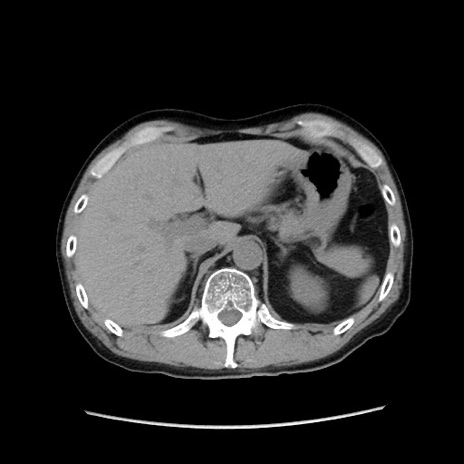

症例37(横断像)

【症例】40歳代 男性

【主訴】腹痛

【現病歴】4時間ほど前に電車に乗車中に臍部上より腹痛出現。徐々に増悪し起立困難となり、救急外来受診。生ものは数日食べていない。今朝お雑煮を食べた。

【身体所見】BT 36.8℃、BP 117/84mmHg、HR 91/min、SpO2 97%、苦悶様、腹部:臍上部広範囲圧痛あり、反跳痛±

【データ】WBC 8100、CRP 0.03